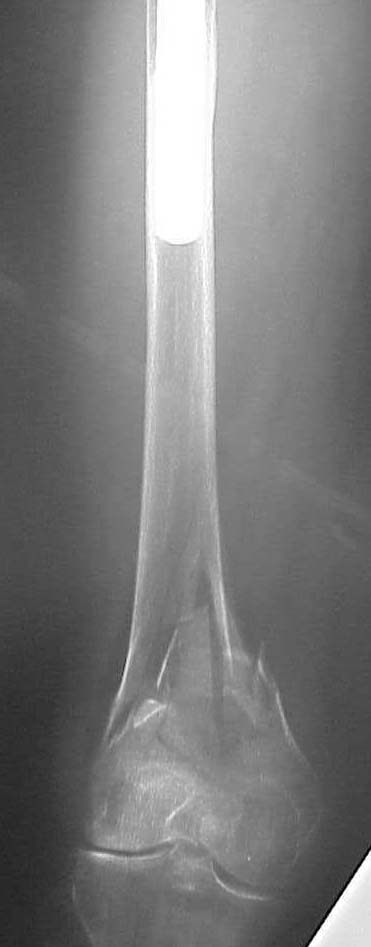

Please see attached pics of an 82 yo woman who lives independently and is a community ambulator s/p low energy fall w/ SC femur fx below a stable uncemented THA (1990).

Looks like SupraCondylar, and IntraCondylar involvements.

This patient generated much discussion at our institution whether a retro IMN, blade plate or LISS would be appropriate. The notch is 17 cm from the tip of the THA and I felt that the stress riser could be a problem and would feel terrible if she broke b/t the implants. The THA is so large that a blade or LISS would be difficult to get proximal purchase.